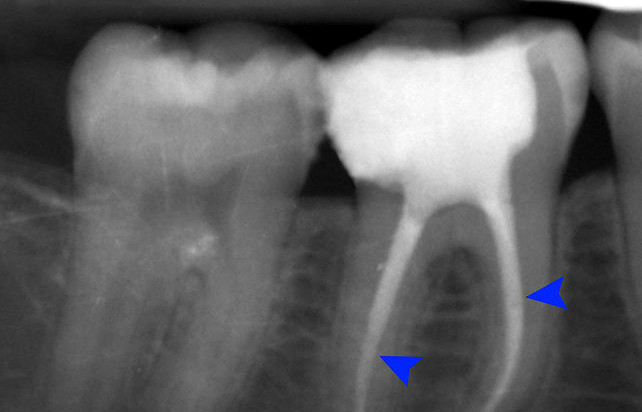

L'Endodonzia è il settore dell'odontoiatria che tratta la terapia dello spazio interno dell'elemento dentale, cioè la polpa dentaria che comprende vasi sanguigni e centri nervosi.

Si ricorre ad essa nei casi in cui la carie o anche altri traumi provochino lesioni talmente profonde da interessare appunto il tessuto pulpare (più noto come nervo del dente).

In questi casi si agisce in maniera diversa dalla conservativa, e l'intervento più frequente è

la Cura Canalare, cioè si procede alla

devitalizzazione del dente.

Ma con le moderne procedure, anche con una cura canalare si ottengono risultati eccellenti sia dal punto di

vista curativo che estetico.

Come si procede?

La cura canalare (o Devitalizzazione) consiste nella rimozione del nervo dentale infetto

o infiammato, e nella sua sostituzione con un'otturazione permanente composta da un cemento canalare

autoindurente e una gomma termoplastica (guttaperca).

Dopo aver ricostruito la corona, il risultato è un dente che non sarà più un serbatoio di batteri soggetto a possibili infezioni, ma una struttura che svolgerà le stesse funzioni di un dente sano!